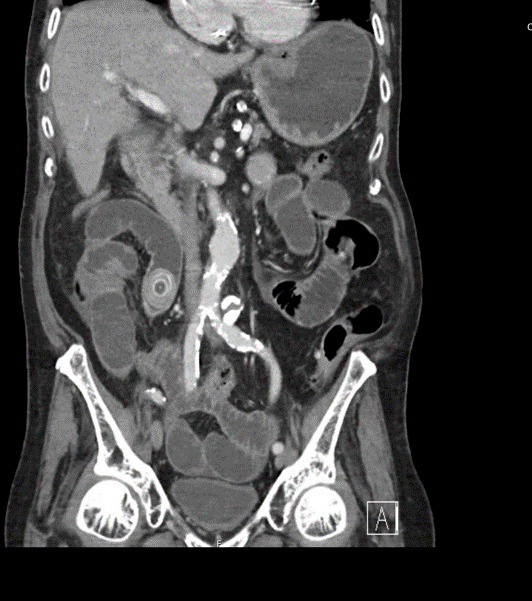

EXPLANATION -There are multiple dilated loops of small bowel secondary to small bowel obstruction. There is mild mural thickening in the right lower quadrant, suggestive of early ischemia. An abrupt transition is seen in the terminal ileum due to a 30 mm gallstone – a gallstone ileus.

Pneumobilia is present, this is secondary to a cholecystoduodenal fistula.

Gallstone ileus is an uncommon but potentially serious cause of small bowel obstruction.

- It occurs when a gallstone enters the small bowel via a biliary-enteric fistula, causing a mechanical bowel obstruction.

- The site of obstruction is the terminal ileum in 50-70% cases (as in this case), 90% of stones over 2cm in diameter cause obstruction. There may be colicky, often periumbilical, abdominal pain, distension, constipation, nausea and vomiting.

- Current surgical options are simple enterolithotomy (as in this case); enterolithotomy, cholecystectomy and fistula closure (one-stage procedure) or enterolithotomy with cholecystectomy performed later as a two-stage procedure.

- This patient went for urgent laparotomy. A 3cm gallstone was found in the distal ileum. The gallstone was able to be moved proximally, and an enterotomy was performed for removal of the gallstone via the ileum.